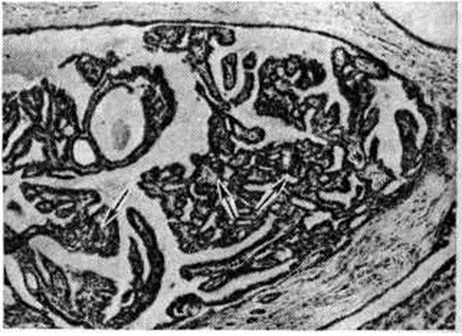

Гистологический изменения складываются из признаков аденоза, склероза, расширения протоков с очагами пролиферации эпителия, комбинирующихся в каждом случае в различных соотношениях, чаще с преобладанием одного из компонентов. Непролиферативная форма Мастопатия характеризуется разрастаниями плотной, нередко гиалинизированной соединительной ткани, в которой располагаются атрофичные дольки и кистозно расширенные протоки, выстланные атрофичным или светлым апокринизированным эпителием (рисунок 1), местами образующим мелкие сосочки. Расширенные протоки могут быть выстланы пикнотичным или вакуолизированным эпителием со слущиванием части клеток и образованием «молозивных телец»; вокруг протоков определяется очаговая лимфоплазмоклеточная инфильтрация с картиной так называемый плазмоклеточного мастита.

Пролиферативная форма Мастопатия характеризуется сочетанием различных вариантов эпителиальной, миоэпителиальной и фиброэпителиальной пролиферации. При эпителиальной пролиферации возникают аденит или мазоплазия (физиологический гиперплазия долек с начальными патологический изменениями) с резко увеличенными, правильно сформированными железистыми дольками. В поздних стадиях Мастопатия на фоне этих изменений обнаруживаются другие морфологический проявления процесса: кисты, цистаденопапилломы и другие При другом варианте эпителиальной пролиферации отмечаются разрастания протокового и долькового эпителия. Возникающие при этом внутрипротоковые пролифераты имеют вид сосочков, криброзных разрастаний и солидных полей, образованных мономорфным, иногда двухрядным, цилиндрическим эпителием с признаками секреции (рисунок 2). Пролиферация внутридолькового эпителия приводит к образованию многослойной эпителиальной выстилки. Внутрипротоковые и дольковые пролифераты склонны к малигнизации и расцениваются большинством авторов как предраковые изменения.